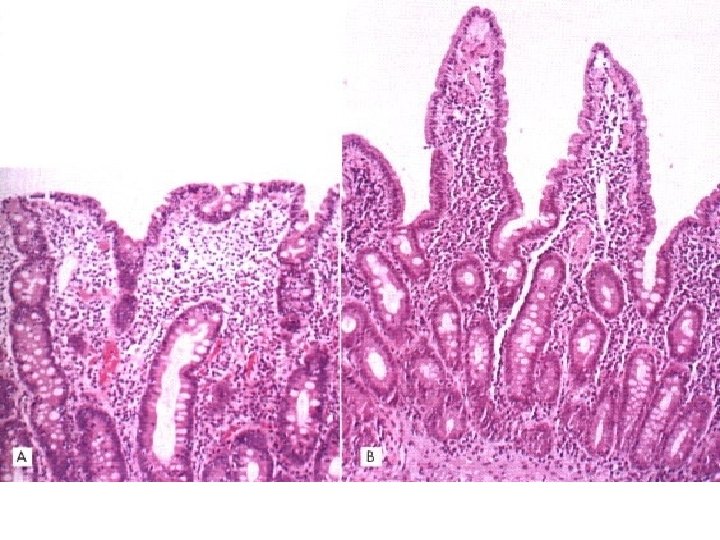

Biopsiile digestive • Biopsiile jejunale: sunt utilizate pentru a face diagnosticul formelor semi-retardate sau retardate de I. P. L. V. : atrofie vilozitară de grade diferite, o accentuare a mitozelor la nivelul criptelor şi o infiltraţie limfocitară T în lamina proprie şi la nivelul epiteliului • biopsiile gastrice: pot confirma diagnosticul gastritei cu eozinofile • rectosigmoidoscopia: efectuată în faţa semnelor clinice evocatoare în mai mult de 80% din cazuri arată semne histologice moderate de inflamaţie şi în 7% din cazuri o “prindere” colică severă superpozabilă recto-colitei hemoragice.